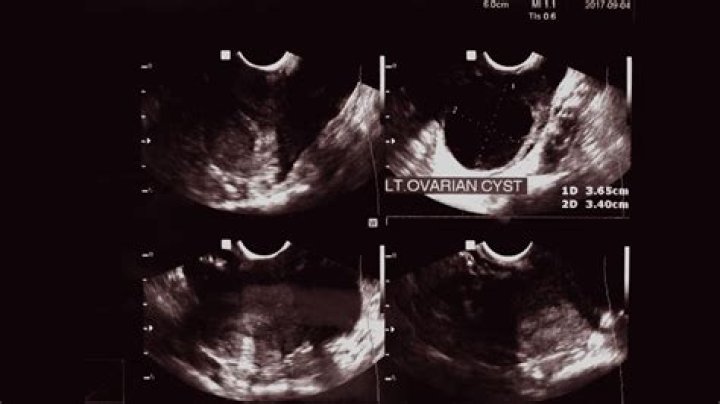

What causes increased ovarian volume?

An enlarged ovary is an ovary that has expanded past its normal size. The cause of this enlargement is often cyst formation. Other causes include endometriosis, benign tumors and, rarely, ovarian cancer. Many types of cysts can grow within the ovary, such as those called functional cysts that form during menstruation.